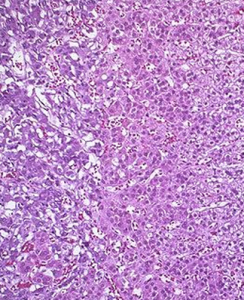

束狀帶,指的是位於腎上腺皮質中間,最厚,約占皮質厚度78%,細胞較大,呈多邊形,胞核染色淺,位於中央。

電鏡下,滑面內質網遠較球狀帶為多,常環繞脂滴和線粒體排列,粗面內質網也較發達。細胞排列成單行或雙行的細胞索,由皮質向髓質呈放射狀排列。索之間有少量血竇和少量結締組織。束狀帶細胞分泌糖皮質激素